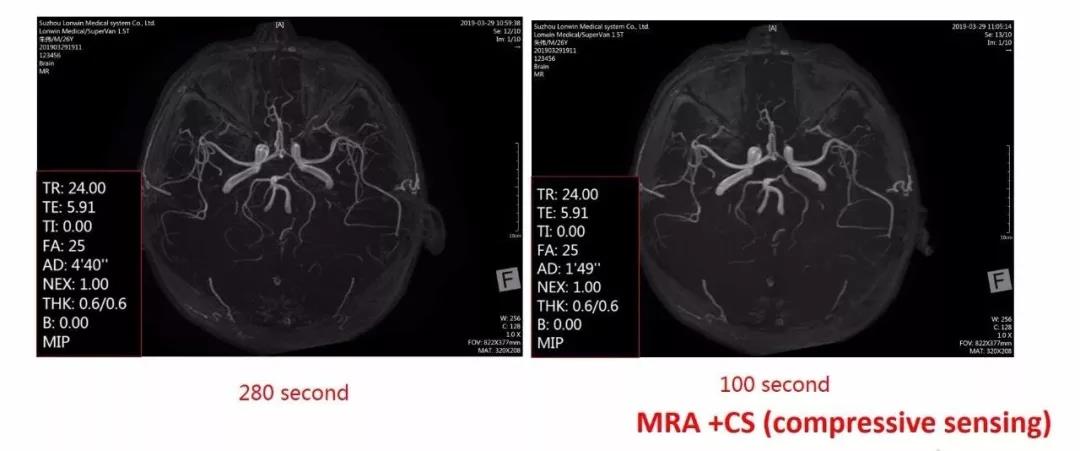

另外Supervan 1.5T还具有100s MRA, 采用压缩感知技术,快速实现脑血管畸形的筛查;MRS技术实现脑组织代谢物的化学成分和含量的检查;Tornado去运动伪影技术,提升成像质量。